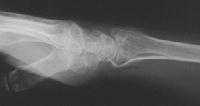

Clinical Example: Distraction plate fixation distal radius fracture

distal radius fracture

distraction plate